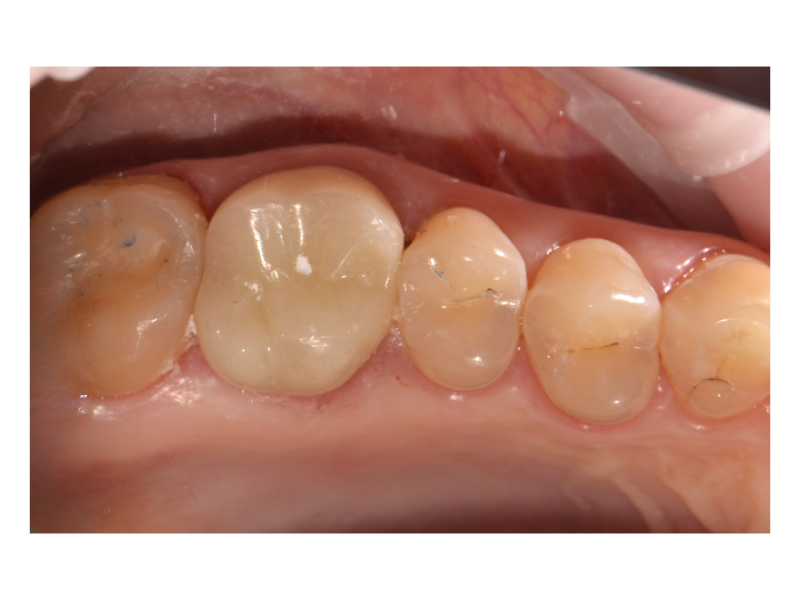

Установка коронки на зуб

Пациент обратился с разрушенным зубом ниже уровня десны из-за кариеса. Задача — восстановить зуб и укрепить его для дальнейшего протезирования. На первом этапе терапевт восстановила зуб с пломбой, так как зуб был мёртвым и большая часть его объёма занимала пломба. Для укрепления зуба была выбрана коронка. Проведена обточка зуба и даны время для заживления десны. В дальнейшем сняты слепки, проведена примерка и зафиксирована коронка

Доктор: Нурисламов Фадис Фирдависович